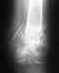

Доброго времени суток! Просьба подсказать, возможно ли восстановление или протезирование полностью отсутствующего (на снимке) надколенника коленного сустава?

Травма произошла после ДТП и сопровождалось значительными ожогами тела. Изначально врачи боролись с ожогами, на тот момент небольшой верхний фрагмент надколенника еще присутствовал. Но по каким то причинам после заживления ожогов и ран сейчас на снимке его вообще не видно. В Иркутске операции с отсутствующим надколенникам не проводят. Хотелось бы узнать какие меры лечения принимать и в каких областях России могут проводить такие операции?